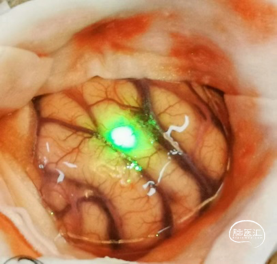

术中:

【暴露肿瘤】

【观察肿瘤】

综合以上情况,考虑该患者适合机器人导航精准定位,在内镜微创下进行手术治疗。这样可以采用直切口,小骨窗,最小程度减少对脑皮层损伤,保护语言和视野,同时可以加快患者的恢复,减少发生皮下积液和延迟出院的几率。

收集MRI及定位CT数据,用睿米机器人进行数据融合,靶路径设计,完成术前计划。